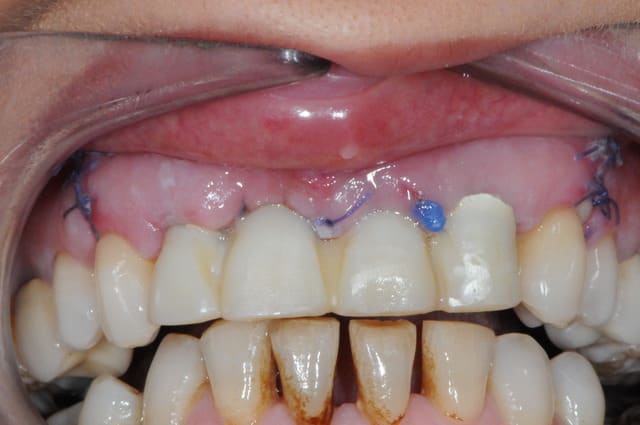

la prothèse immédiate grâce aux empreintes de départ.

ici la résine c'est du protemp 4, c'est super mais un peu gras.